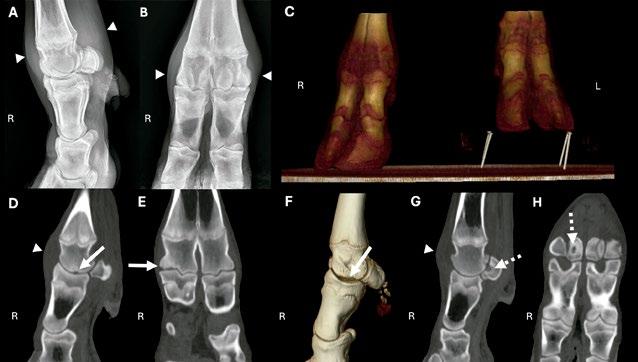

Imagen 2. Imágenes de TC en estación de la cabeza de un bovino que muestran una calidad de imagen representativa en una reconstrucción multiplanar sagital (A) y una imagen tridimensional del cráneo con renderizado volumétrico (B). Las imágenes transversales de TC centradas en la bulla timpánica de cuatro terneros diferentes muestran una bulla timpánica normal (C) y casos de otitis media (D a F), evidenciada por la presencia de material con atenuación de líquido en la bulla timpánica (flechas negras) y por el engrosamiento y la esclerosis de las paredes de la bulla timpánica (cabezas de flecha blancas). En uno de los terneros se observó la presencia de líquido en los conductos auditivos horizontales, compatible con otitis externa (E; flechas blancas), y en otro ternero se detectó una lisis focal de la bulla timpánica izquierda (L), compatible con osteomielitis (F; cabeza de flecha negra). Todas las imágenes de TC se obtuvieron utilizando un algoritmo óseo de alta frecuencia (ancho de ventana/nivel de ventana [WW/WL], 1.500/300).

Imagen 3. Radiografías (A y B), imágenes de TC con renderizado volumétrico tridimensional (C y F) e imágenes de TC en estación (D, E, G y H; algoritmo óseo de alta frecuencia en ventana ósea; WW/WL, 1.500/300) de la articulación metacarpofalángica derecha (R) en un ternero macho frisón de 10 meses de edad. Las radiografías laterolateral (A) y dorsopalmar (B) muestran un engrosamiento de los tejidos blandos intracapsulares centrado sobre la articulación metacarpofalángica (cabezas de flecha), sin identificarse alteraciones óseas. La reconstrucción tridimensional con renderizado volumétrico en plano dorsal de las extremidades distales derecha (R) e izquierda (L) muestra el posicionamiento en el escáner de TC en estación (C); se utilizó un bloque en la extremidad torácica izquierda para facilitar la carga de peso. Se presentan imágenes de TC con reconstrucción multiplanar sagital (D y G) y dorsal (E y H), así como una reconstrucción tridimensional con renderizado volumétrico en plano sagital (F) de la articulación metacarpofalángica derecha. La letra R indica los aspectos dorsal o lateral de la extremidad. El margen articular de la articulación metacarpofalángica del dígito lateral (cuarto metacarpiano fusionado) presentaba una irregularidad con un defecto cóncavo y esclerosis del hueso subcondral (D a F; flechas blancas). Además, se observó un defecto cóncavo hipoatenuante rodeado de esclerosis en el aspecto dorsal del sesamoideo proximal medial del dígito lateral (G y H; flechas blancas discontinuas). En la TC se identificó derrame articular metacarpofalángico (D y G; cabezas de flecha blancas). Los hallazgos fueron compatibles con una osteocondrosis de la articulación metacarpofalángica confirmada mediante artroscopia y con una lesión ósea tipo quiste del sesamoideo proximal medial.

Imagen 4. Radiografías (A-C), imagen de TC en estación con renderizado volumétrico tridimensional en plano sagital (D) e imágenes de TC en estación (E y F) obtenidas con un algoritmo óseo de alta frecuencia en ventana ósea (WW/ WL, 1.500/300) de la articulación metacarpofalángica izquierda (L) y la pezuña de un macho caprino castrado de 7 años con cojera crónica del miembro torácico izquierdo. La letra L indica los aspectos dorsal y lateral de la extremidad. En la revisión inicial no se identificaron alteraciones en las radiografías dorsopalmar (A), laterolateral (B) y oblicua lateral (C). La reconstrucción tridimensional con renderizado volumétrico en plano sagital (D), la reconstrucción multiplanar sagital (E) de la pezuña lateral y la imagen transversal de TC de los dígitos distales (F) revelaron una fractura articular crónica no desplazada de la tercera falange de la pezuña lateral (flechas). Tras la reevaluación de las radiografías después de la TC, se identificó en esta localización una línea radiolúcida incompleta y mal definida en la radiografía oblicua lateral (C; cabeza de flecha blanca).